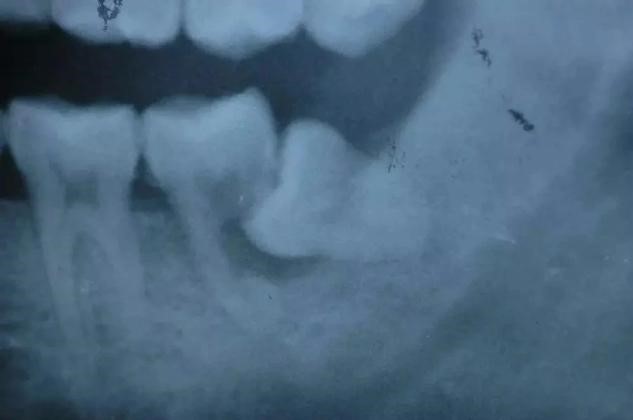

2、磨牙龋齿:对于向前倾斜的阻生智齿,食物通常积聚在相邻牙齿之间,这容易导致相邻牙齿(下第二磨牙)的龋齿。这种龋齿不容易被发现,一旦出现疼痛(急性牙髓炎),牙冠通常会严重受损。出现龋齿、牙髓炎,甚至牙齿不能保留。第二磨牙缺失对咀嚼功能有很大影响,也很难用义齿修复。